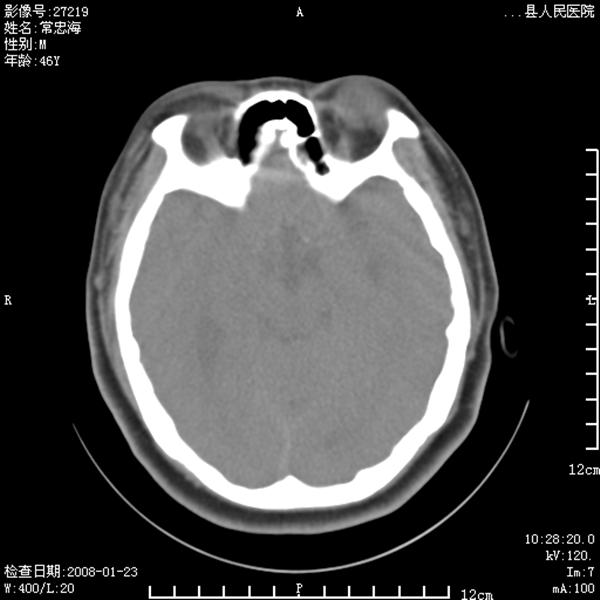

以下是引用江边学者在2008-4-19 22:26:00的发言:[br]1.胼胝体发育不良。[br]2.右侧眼球痨。[br]3.右侧颜面部软组织挫伤。